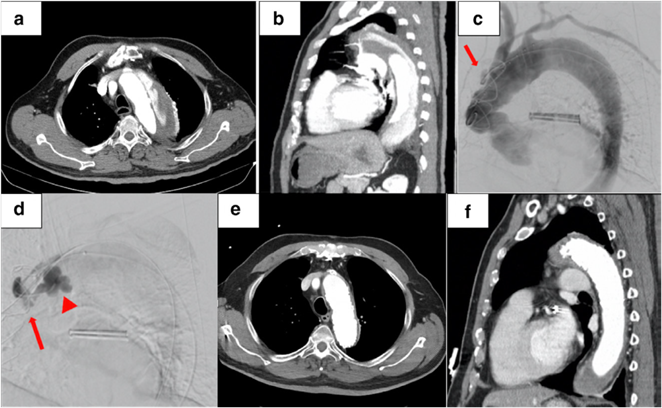

病例1为72岁的男子曾因AAA接受治疗,被诊断为70 mm的Ⅲb型主动脉夹层。使用Amplatzer血管塞封闭了5 mm内膜破口,成功修复。患者顺利出院,无并发症,随访CT显示,血管塞无移位,主动脉直径变小。

病例2为75岁女性因Stanford A型主动脉夹层行紧急升主动脉置换手术,残留降主动脉破口。使用AVP Ⅱ顺利栓塞破口,随访影像显示假腔血栓化。

病例3为79岁男性,患者有DeBakey Ⅰ型主动脉夹层。患者不耐受开放手术,使用AVP栓塞近端破口,顺利实现封堵。随访CT显示假腔血栓化。

综上所述,现有应用AVP栓塞主动脉夹层裂口的病例报告表明了该技术的可行性和有效性。该技术操作简便易行,疗效显著,是否常规应用取决于病变本身特点,包括解剖学条件,患者的自身情况、裂口大小等。后期还需要大规模前瞻性研究以改写或增补指南。